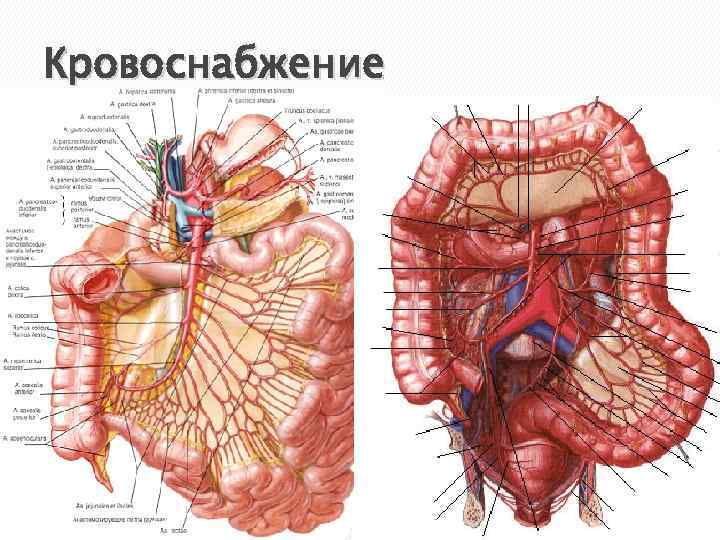

Кровоснабжение

Кровоснабжение